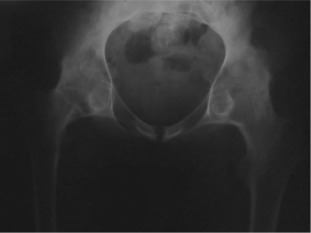

Four years after bilateral simultaneous THA.

Fig. 2.

There were 61 patients (50 male, 11 female) with 105 affected hips (72% bilateral, 28% unilateral). The average patient age at surgery was 41.3 ± 10.2 years old. The age of patients at THA was as follows: <30 years for 14 patients (23 hips), 31–50 years for 41 patients (73 hips) and >50 years for 6 patients (9 hips) (Graph 1 ). The younger age at diagnosis (<30 years old) of AS was correlated with younger age at THA (p < 0.05). Bone ankylosis was detected in 37 (35%) and acetabular protrusion was noticed in 18 (17%) hips in pre-operative radiographs (Fig. 1 , Fig. 2 , Fig. 3  ;  Fig. 4 ) (Table 1 ). The mean pre-operative flexion contracture was 20.3°±21.8°. In patients without ankylosis, the mean total hip range of motion (ROM) was 67.8°±25.7°.